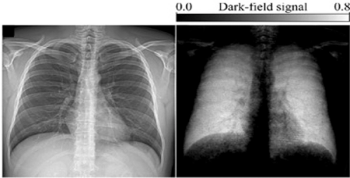

X-ray dark-field chest imaging may generate detailed imaging of lungs without interference from surrounding tissue or influence by characteristics such as age, gender or weight.